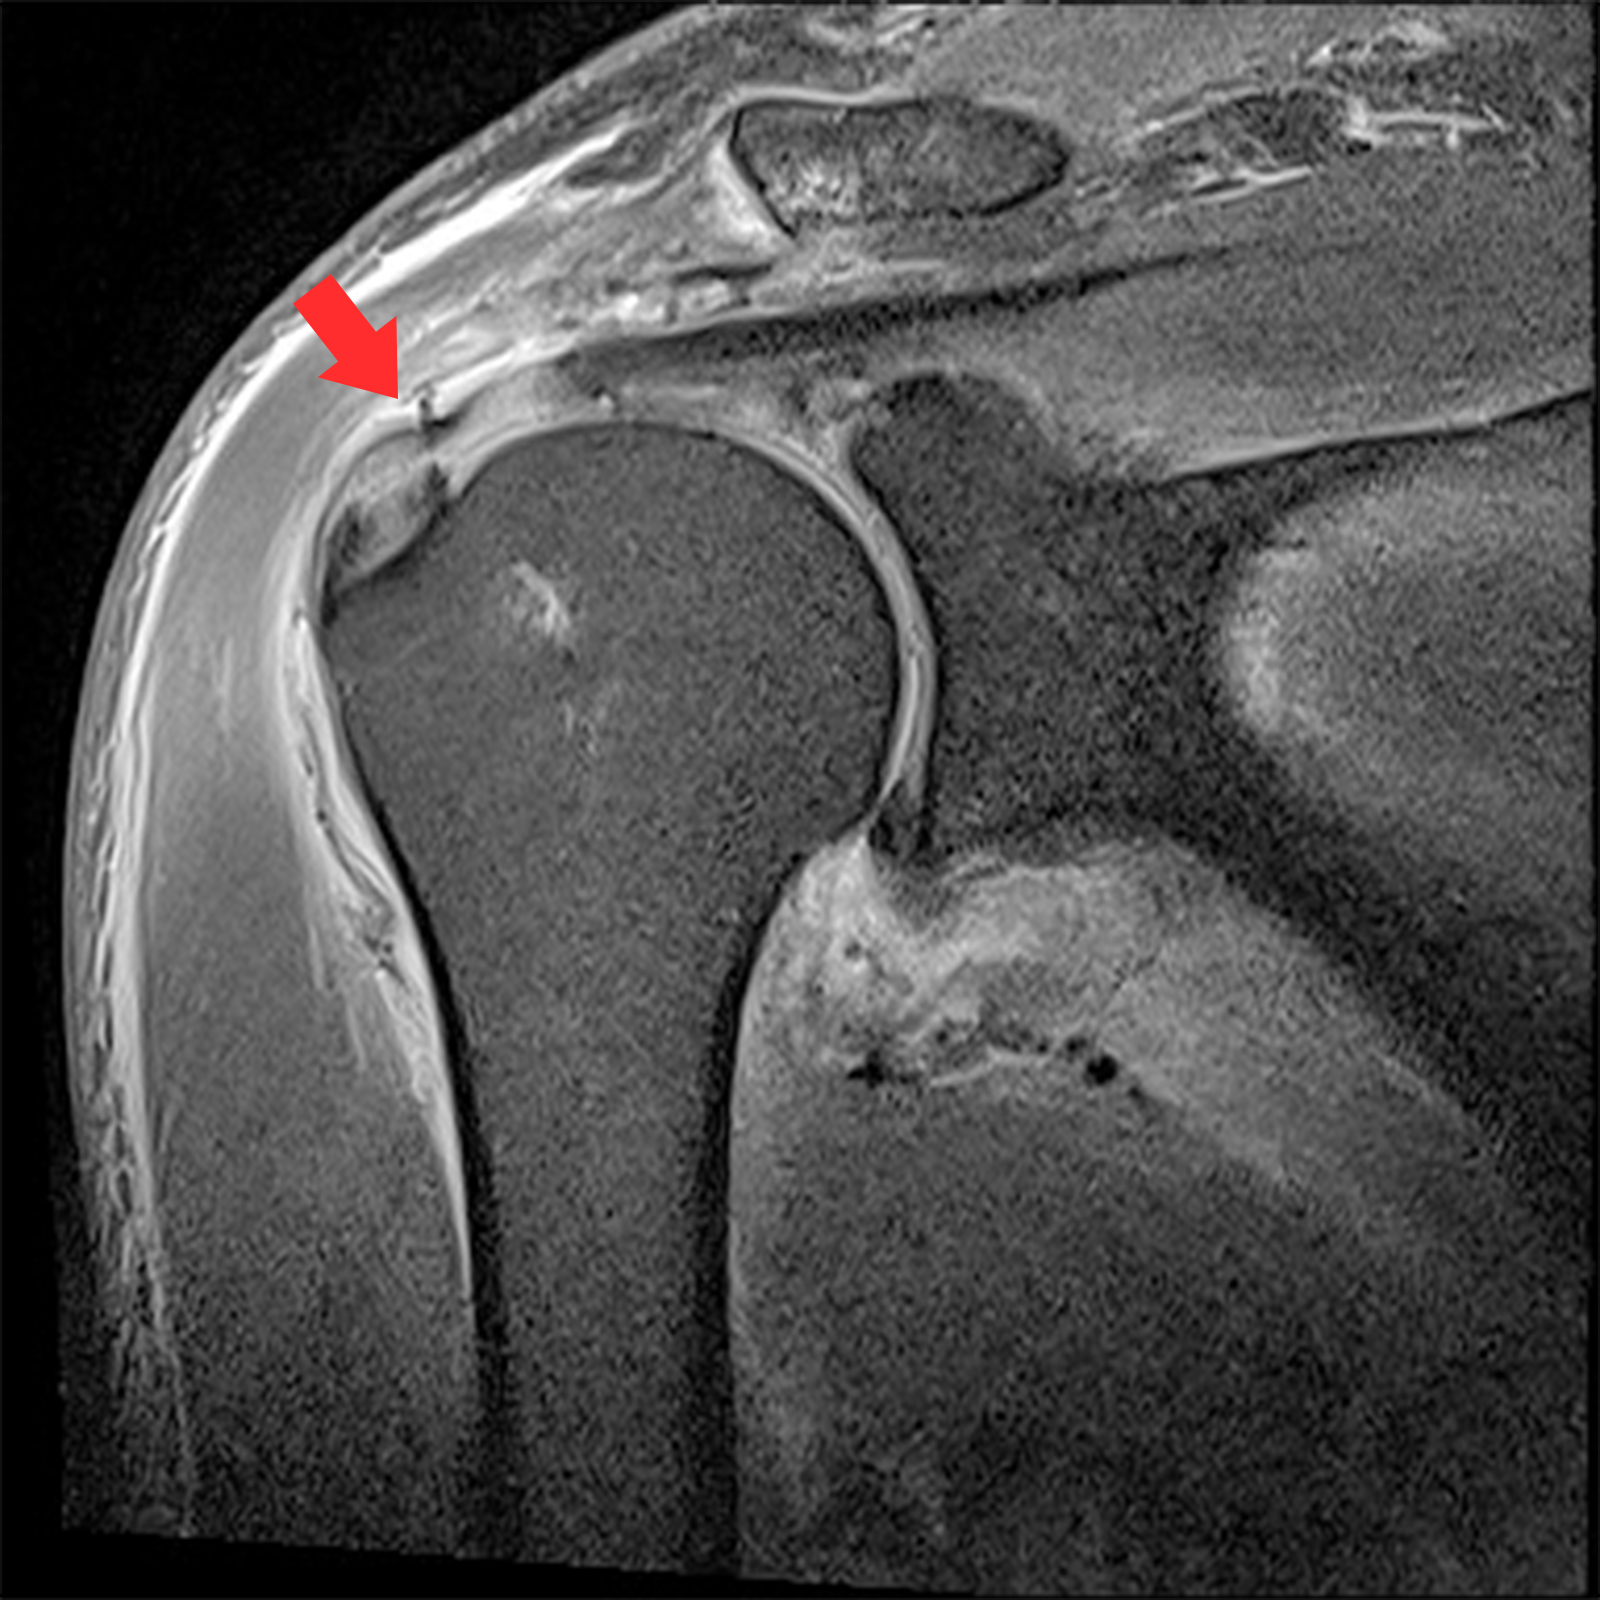

MRI 촬영시 정상적인 어깨의 경우 회전근개가 까맣게 나타나지만, 파열된 경우 하얗게 보여짐

관절내시경 수술 전

찢어지고 파열된 회전근개 모습

2022.06.15